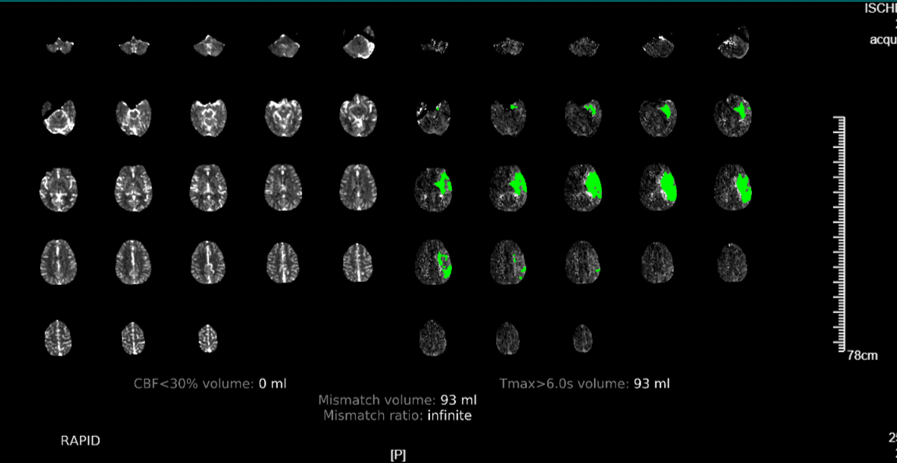

近期,我院高級(jí)卒中中心引進(jìn)了腦卒中頭顱“一站式”ct檢查又稱多模式頭顱ct成像,包括ct平掃(ncct),ct血管成像(cta)和ct灌注成像(ctp)。目前省內(nèi)僅有我院及中南大學(xué)湘雅醫(yī)院、湘潭市中心醫(yī)院三家醫(yī)院應(yīng)用了該項(xiàng)技術(shù)。該項(xiàng)技術(shù)的目的是擴(kuò)大取栓治療時(shí)間窗,使更多的患者從取栓治療中獲益。通俗的說(shuō),“時(shí)間就是大腦”的搶救理念倡導(dǎo)的是,一旦發(fā)生卒中征兆,立即送至有靜脈溶栓、機(jī)械取栓資質(zhì)的醫(yī)院救治。對(duì)于明確發(fā)病4.5h以內(nèi)的急性缺血性腦卒中患者,來(lái)了醫(yī)院之后先做一個(gè)ct平掃檢查,排除腦出血的情況,在無(wú)禁忌癥的前提下,建議實(shí)施靜脈溶栓治療,早發(fā)現(xiàn)早治療早獲益。但是對(duì)于發(fā)病6-24h的患者或發(fā)病時(shí)間不明確的患者,ct平掃上是很難看到梗死表現(xiàn),梗死的表現(xiàn)一般到24小時(shí)之后才會(huì)出現(xiàn)。那怎么來(lái)顯示這部分組織?那就是進(jìn)行“ct灌注成像”,可以看到具體的梗死區(qū)域、可挽救的缺血半暗帶、同時(shí)利用ctp數(shù)據(jù)進(jìn)行頭部cta重建和側(cè)枝循環(huán)評(píng)估,為下一步的治療方案提供量化標(biāo)準(zhǔn)。但是做ct、cta再做ctp無(wú)疑時(shí)間線就拉長(zhǎng)了,與“時(shí)間就是大腦”的理念相違背。那有沒(méi)有一項(xiàng)技術(shù)將這三項(xiàng)檢查緊密聯(lián)系起來(lái),有效縮短檢查時(shí)間?這便是頭顱“一站式”ct檢查,既為腦卒中患者的救治贏得了寶貴的時(shí)間,又如同徠卡相機(jī)一樣精準(zhǔn)、高清的成像,幫助醫(yī)生快速擬定治療方案。

多模式頭顱ct成像和側(cè)枝循環(huán)評(píng)估